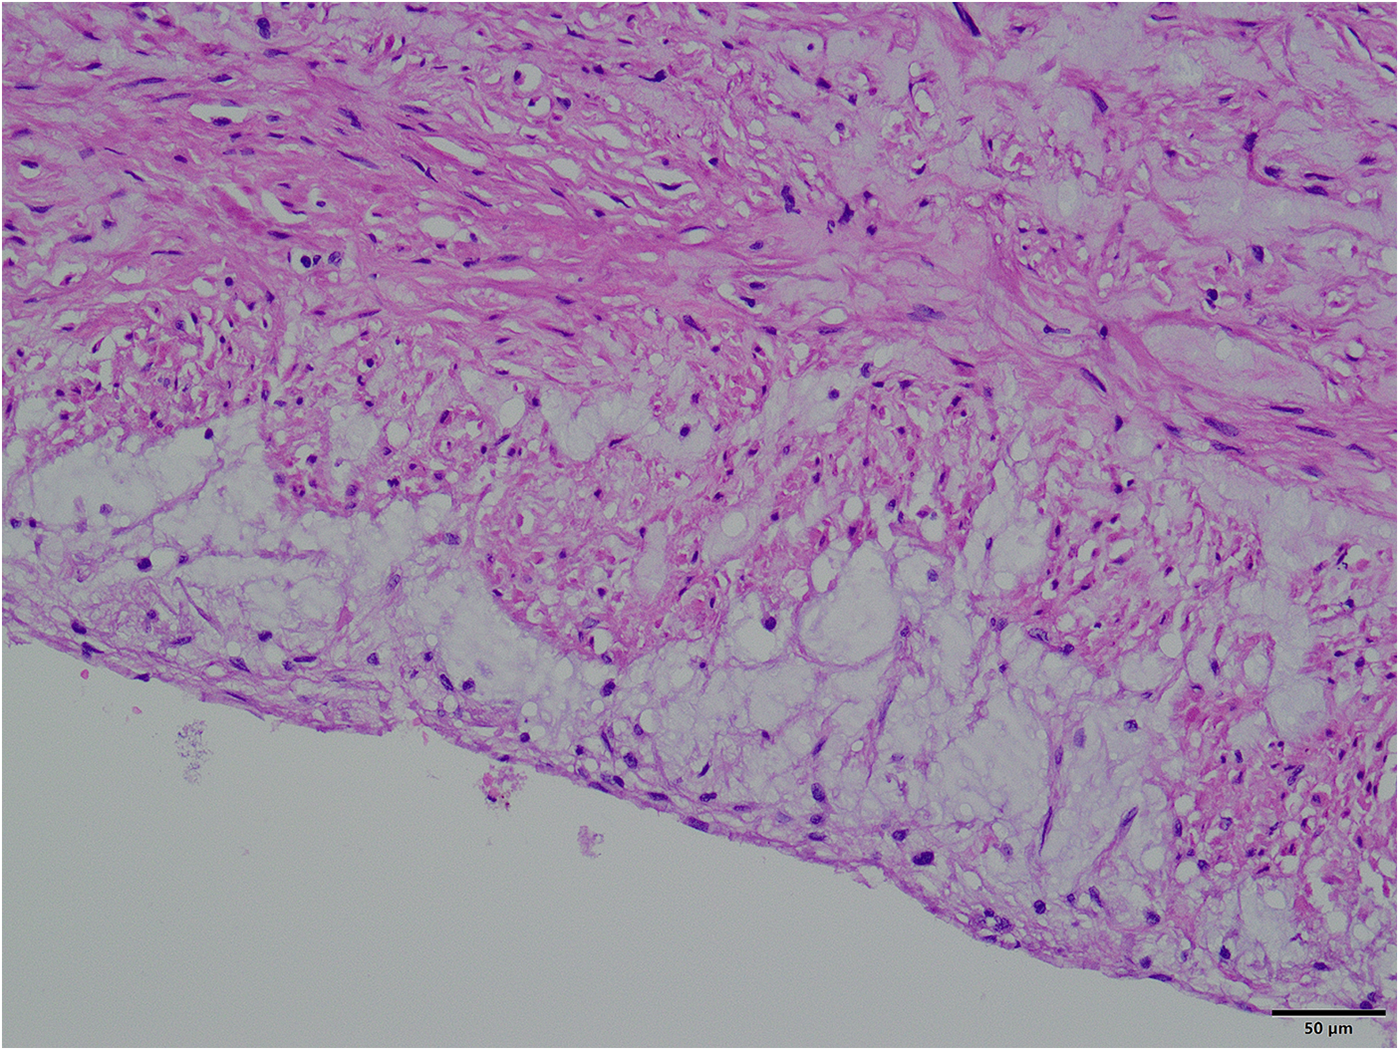

The surgical approach for this patient was the conventional method usually used by our team for second sternotomy surgery. However, some aspects are worth analyzing. One question is why the aneurysm grew so large in 20 years. Patients with some diseases, such as Marfan syndrome, vascular Ehlers-Danlos syndrome, Turner syndrome, and Loeys-Dietz syndrome, have a high risk of aneurysm expansion, dissection, and rupture (3, 4). The patient in this case had a congenital aortic developmental abnormality and had undergone surgical treatment. However, since the diameter of other blood vessels was normal (including at the site of the previous surgery), the ascending aortic tissue could have had a congenital developmental abnormality. Our pathology report also indicated that the ascending aortic wall had fibrous connective tissue hyperplasia and lacked normal elastic fiber tissue (Figure 5). During surgery, we found that the patient's previous surgical incision had shifted to the posterior wall of the aneurysm (Figure 3A), indicating that the enlargement of such a large aneurysm may be asymmetric, not coaxial, and is the first time this phenomenon was observed in such patients. The fact that such a large aneurysm grew in such a slender patient without rupture may be related to the patient's previous cardiac surgery, in which adhesions formed around the aorta, preventing acute rupture (5, 6).

Figure 5

Pathological picture of the aneurysm wall (×400).